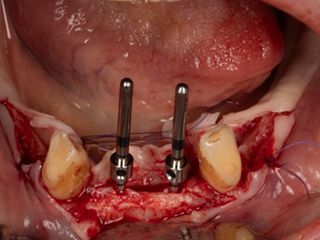

3c. Two mini-implants with a diameter of 2.6 mm and a length of 12 mm were placed in positions 32 and 42, first manually and then using a contra-angle. The insertion torque recorded at the end of the procedure was 21 N.cm in 32 and 17 N.cm in 42. The implants were positioned 0.5 mm subcrestal, i.e. with slight burial of the smooth neck.

3c

3d

3d. Two mini-implants with a diameter of 2.6 mm and a length of 12 mm were placed in positions 34 and 44 using the same protocol as for the previous mini-implants. The torque obtained was 27 Ncm in 34 and 37 Ncm in 44.

3e. Canines 33 and 43 were extracted and the burial of the implants was then checked.

3e